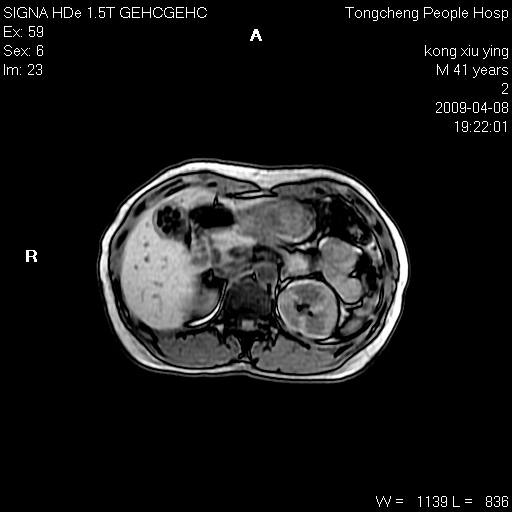

标题: CL1008:【经典】胆囊石榴籽样结石。 [打印本页]

标题: CL1008:【经典】胆囊石榴籽样结石。

女,41岁。健康体检——彩超提示:胆囊显示不清。平素健康,无不适感。

腹部mr扫描及mrcp,图像如下:

胆囊石榴籽样结石。